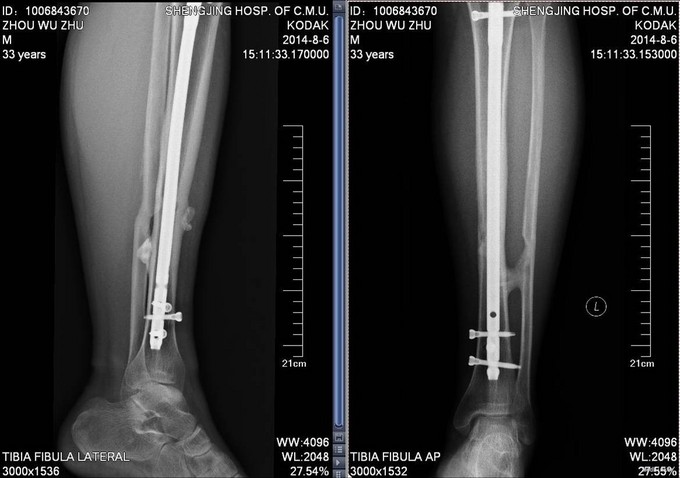

患者2012年8月发生车祸,致右股骨及左胫骨骨折,后于我院行右股骨骨折闭合复位内固定术,左胫骨骨折闭合复位内固定术,手术顺利,安返病房,术后康复锻炼,定期复查,近期复出X线,提示骨折愈合良好,今日门诊以“右股骨骨折,左胫骨骨折术后”为主要诊断收入我科

患者步入病房,神志清,右大腿压痛叩击痛(—),左小腿压痛叩击痛(—)。双下肢等长。双下肢感觉运动均正常。

入院后完善检查,查无手术禁忌症后右股骨干骨折术后内固定物取出术,左胫骨骨折术后内固定物出去术,术后第二天自动退院。